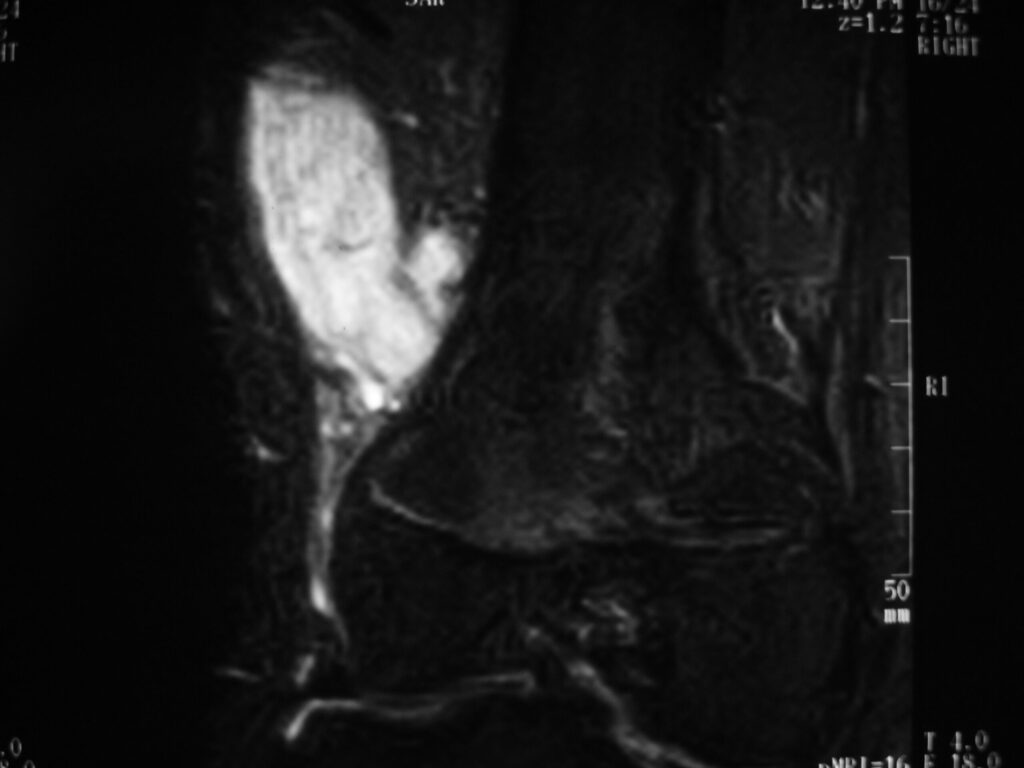

MRI

Shows multiloculated, heterogeneous mass.

“Triple Signal Intensity sign”; hypointense, isointense and hyperintense with fat on T2 – weighted MRI imaging. This sign is present in 30 to 50% of the cases. (Fig.3)

Under contrast enhancement Synovial Sarcoma appears heterogeneous and demonstrate areas of nodular enhancement.

In approximately 30% of cases a multiple vascular cannel may be identified

Synovial sarcomas may have a cystic appearance and are often mistaken for ganglion cysts especially those adjacent to tendons and in the foot and ankle.